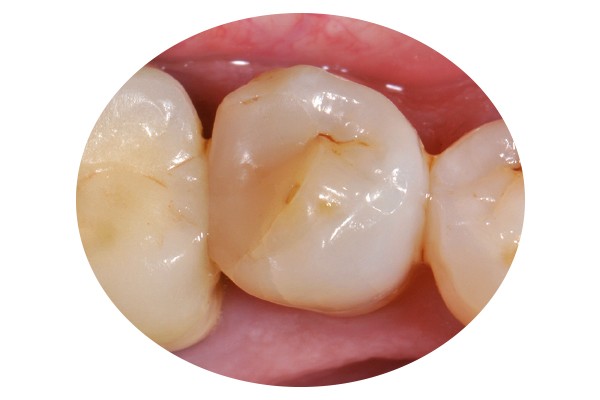

34, 35. Vues vestibulaire et occlusale de la prothèse d’usage collée sur 45 (Laboratoire du Sud-Ouest).